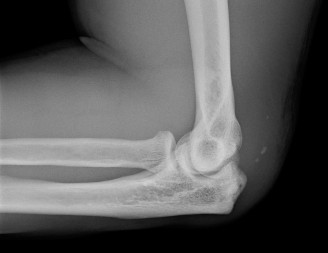

You send the patient for an MRI, which is shown in Figure 2–66.

Figure 2–66

Based on the clinical examination and imaging, what is the most likely etiology of the patient’s symptoms?

The correct answer is (C). The patient’s clinical examination findings of isolated

weakness in external rotation and atrophy of the infraspinatus muscle point to suprascapular nerve entrapment at a location past the exit point for the branch to the supraspinatus muscle. Also, MRI reveals a posterior labral tear with a paralabral cyst that is compressing the suprascapular nerve at the spinoglenoid notch. Choice A, while fitting with the patient’s clinical examination, does not fit with the MRI showing paralabral cyst. Choices B and D are incorrect because entrapment of the suprascapular nerve at the suprascapular notch by scapular body fracture or by the transverse scapular ligament (more common) would lead to weakness/atrophy in both supraspinatus and infraspinatus muscles as the suprascapular notch is proximal to the nerve branch point to the supraspinatus muscle.